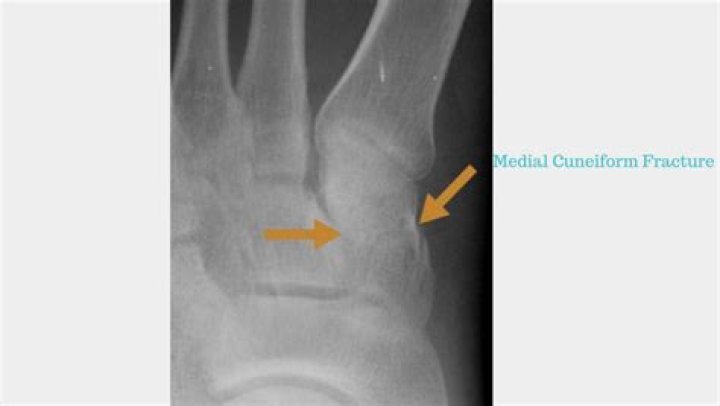

Isolated fractures of the cuneiform bones are rare, and even since the development of advanced diagnostic imaging techniques, reports of isolated fractures remain scarce.

Isolated fractures of the cuneiforms are extremely rare, accounting for only 1.7% of all midfoot fractures.

An isolated fracture of the lateral cuneiform is a rare finding. However, isolated injuries may occur as the result of direct trauma. We report a case of an isolated fracture of the lateral cuneiform that was not seen on initial radiographs and only became evident on plain radiographs 4 weeks after the injury.

How long does a cuneiform fracture take to heal?

Treatment of uncomplicated cuneiform stress fractures depends on severity. Most should improve within 4 to 6 weeks of protected weight-bearing in a fracture boot or with partial weight-bearing, followed by a gradual return to activities over a 4-week period.